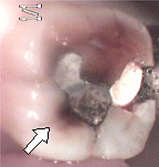

もう1症例ご紹介します。

今度は、歯に詰められた、「アマルガム合金」と言う、水銀化合物の症例です。歯に穴が開いた、と言う訴えで来院されました。

左の画像にある白い矢印のところをご覧下さい。歯に何か染み込んでいるのがお解かりになるでしょうか? これは、水銀化合物が数年の間に溶け出し、歯の中の細い管の中に溶出して、やはり酸化して変色している症例です。

良く見ると、そのほかの部位にも淡い茶色い変色域が透けて見えています。 そして、正に水銀合金の境目から、歯質の破折が起きて、穴が開いたようにも見受けられます。